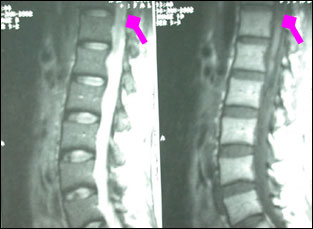

术后图片:肿瘤大部切除。

专家评点:脊髓内胶质母细胞瘤很少见,文献上仅有几篇个例报道,见于圆锥部位的文献上仅有1例。圆锥髓内肿瘤多为室管膜瘤或星形细胞瘤,病程相对较缓,以急性截瘫起病的很少。如碰到类似患者,本着“急性截瘫相当于脑疝”的原则,进行急诊手术切除髓内肿瘤,椎板咬除减压,术后根据肿瘤性质行外放射或化学药物等辅助治疗。